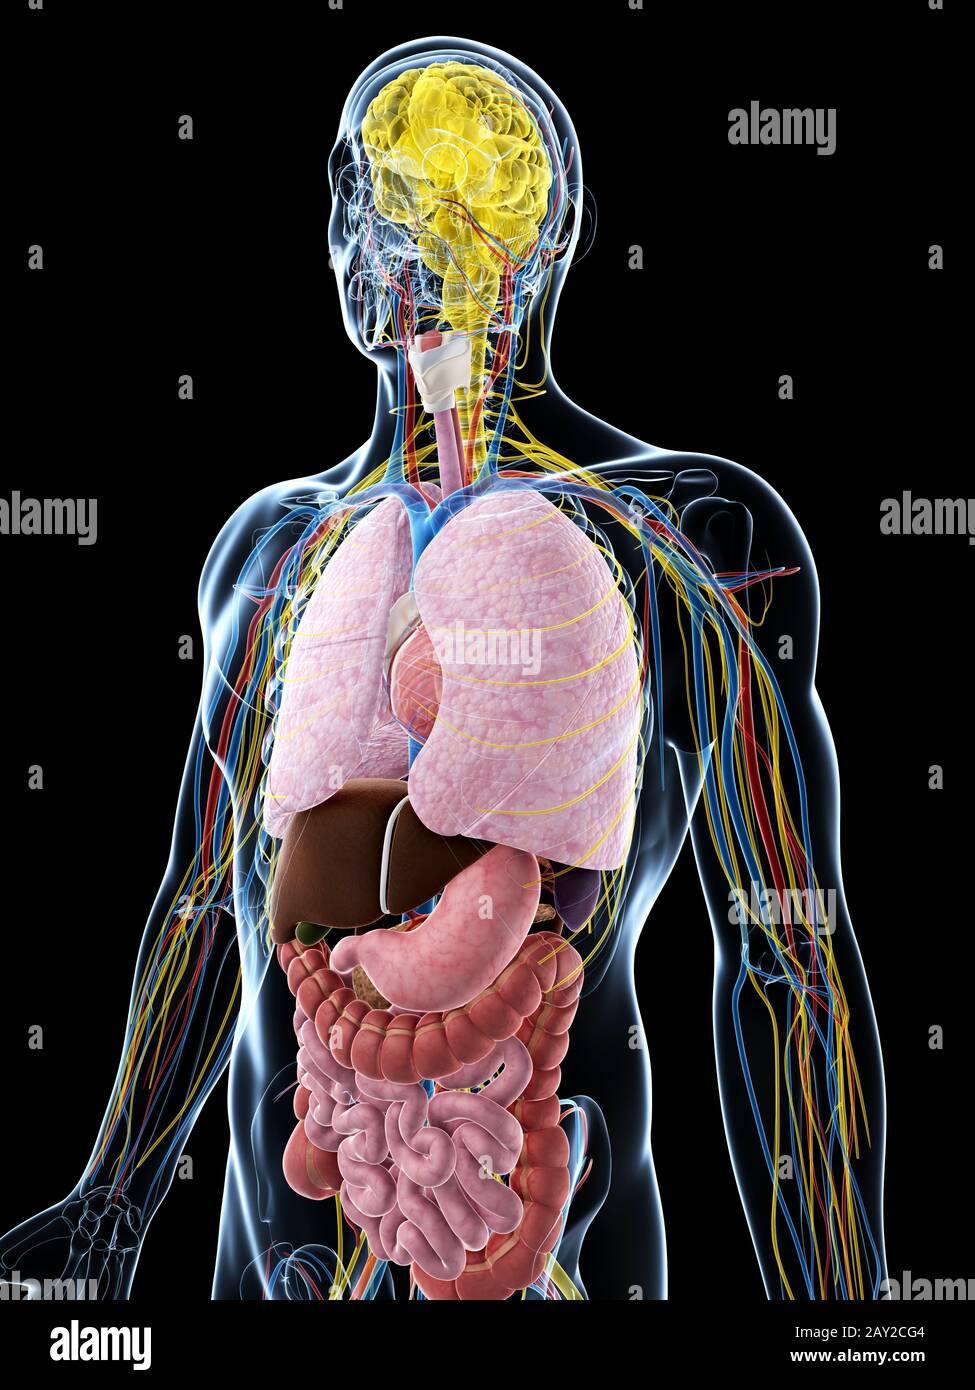

RFDGYRD7–Männliche Anatomie, inneren Organe allein, volle Atmungs- und Verdauungssystem, mit einigen Organen Cutaway. Anatomie-Bild.